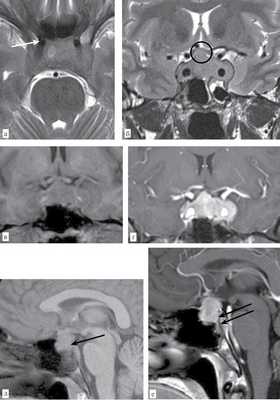

При гистологическом исследовании во всех 4 случаях структура аденогипофиза была нарушена за счет фиброза и гиалиноза (рис. 1). В фиброзированных участках визуализировались отдельные «замурованные» нейроэндокринные клетки и единичные ацинарные структуры, которые экспрессировали цитокератин клона АЕ1/АЕ3, синаптофизин и хромогранин А, СТГ, АКТГ, ТТГ, пролактин, ЛГ и ФСГ (рис. 2). Отмечалась хроническая воспалительная инфильтрация, представленная лимфоцитами, плазматическими клетками, макрофагами. В отдельных полях зрения встречались эозинофильные и нейтрофильные лейкоциты. При иммуногистохимическом исследовании в воспалительном инфильтрате преобладали CD3 + -Т-лимфоциты и CD38 + -плазмоциты (рис. 3), CD8 + -Т-киллеров и CD68 + -макрофагов было значительно меньше. На эндотелии сосудов и в клетках инфильтрата отмечалась экспрессия HLA-DR+++, MHC1++++.

При макроскопическом морфологическом исследовании выявлены множественные мелкие фрагменты серой эластичной ткани по 0,2 см объемом 1 мл. Гистологическое исследование: фрагменты аденогипофиза с диффузно-очаговой лимфоцитарной инфильтрацией, формированием мономорфных «штампованных» гранулем без некрозов со множеством гигантских многоядерных клеток и фиброзом. Окраска на микобактерии по Цилю—Нильсену отрицательная. При иммуногистохимическом исследовании штампованные гранулемы с CD68 + -клетками в центре гранулем и CD3 + -Т-лимфоцитами, с небольшим количеством CD38 + -плазмоцитов по периферии; HLA-DR++++ на клетках инфильтрата и эндотелии сосудов (рис. 5). Среди гранулем трабекулы клеток с экспрессией синаптофизина и хромогранина. Заключение: гистологическая картина вторичного ГГ — саркоидоза гипофиза.

Рис. 5. Больной № 2. Изолированный саркоидоз гипофиза. а — «штампованные» гранулемы одинаковых размеров и строения, окруженные фиброзной тканью; окраска трихромом Массона, ×100; б — в центре гранулем CD68+-макрофаги, ×100.

Мужчина 48 лет с жалобами на снижение остроты зрения на оба глаза, выпадение полей зрения, головокружение, слабость. Из анамнеза известно, что 11 лет назад перенес инсульт в левом каротидном бассейне с развитием правостороннего гемипареза. При проведении МРТ головного мозга выявлено объемное образование хиазмально-селлярной области размерами 24×19×19 мм с интра-, супра-, ретроселлярным ростом. По результатам анализа уровня гормонов в крови отмечалось снижение уровня пролактина (2,9 нг/мл), ЛГ (0,1 мМЕ/мл), показатели остальных гормонов в пределах нормы. Клинические данные говорили о гормонально-неактивной макроаденоме гипофиза. Выполнено тотальное трансназальное эндоскопическое удаление образования.

При макроскопическом исследовании выявлены мелкие фрагменты мягкоэластичной желтой ткани объемом 1 мл. При гистологическом исследовании — большая часть материала представлена белковыми некротизированными массами с единичными фрагментами эпителиальной выстилки из цилиндрического мерцательного эпителия и единичными кристаллами холестерина. По краю некротизированных масс полиморфно-клеточный вал из гистиоцитов с пенистой цитоплазмой, нейтрофилов, эозинофилов, лимфоцитов, плазмоцитов, а также единичные некротизированные нейроэндокринные клетки (рис. 6). При иммуногистохимическом исследовании в инфильтрате преобладали CD68 + — и CD45 + -клетки, меньшее количество CD3 + -Т-лимфоцитов и CD38 + -плазмоцитов. HLA-DR++++ на клетках инфильтрата и эндотелии сосудов. Единичные клетки экспрессировали хромогранин, синаптофизин и цитокератин клона АЕ1/АЕ3. Заключение: разрыв кисты кармана Ратке с нагноением, вторичный ксантоматозный некротизирующий гипофизит.

Рис. 6. Больной № 3. Разрыв кисты кармана Ратке. Ксантоматозный некротизирующий гипофизит. а — некротизированные массы с фрагментом эпителиальной выстилки кисты кармана Ратке; окраска гематоксилином и эозином, ×200; б — полиморфно-клеточный инфильтрат; окраска гематоксилином и эозином, ×400; в — CD68+-ксантомные клетки, ×400.